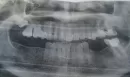

Изначальную причину, которую пытаюсь найти, два месяца никто не видит. На всех снимках присутствует фрагмент, слева от 8-го зуба верхней челюсти справа (ни разу за это время никто из докторов на это внимания не обратил). Только, судя по снимкам, такое ощущение, что при удалении 8-го зуба не заметив этого, часть срезали. Так как на следующих 2-х снимках это есть, но выглядит как будто срезанная половинка.Три панорамных снимка челюсти сделаны с временным промежутком в один месяц.

Что это может быть, то, что между полосками?

Патологии на данном снимке (фрагмент, слева от 8-го зуба верхней челюсти справа) нет, скорее всего, это артефакт рентгенограммы. Чтобы точно в этом убедиться, следует сделать компьютерную томографию. Проконсультируйтесь очно с челюстно-лицевым хирургом.